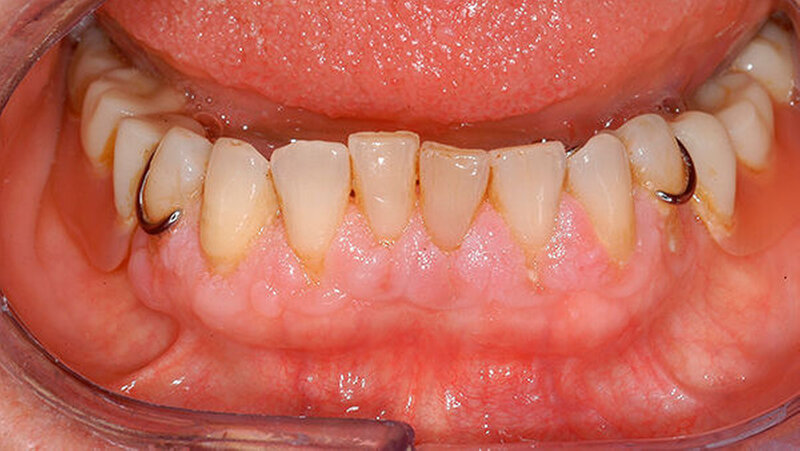

Eine Woche nach Abschluss der internistischen Therapie stellte sich die Patientin zur Verlaufskontrolle in unserer Klinik vor, dabei zeigte sich eine vollständige Remission der hyperplastischen Gingiva bei weiterhin insuffizienter Mundhygiene (Abbildungen 4 und 5).